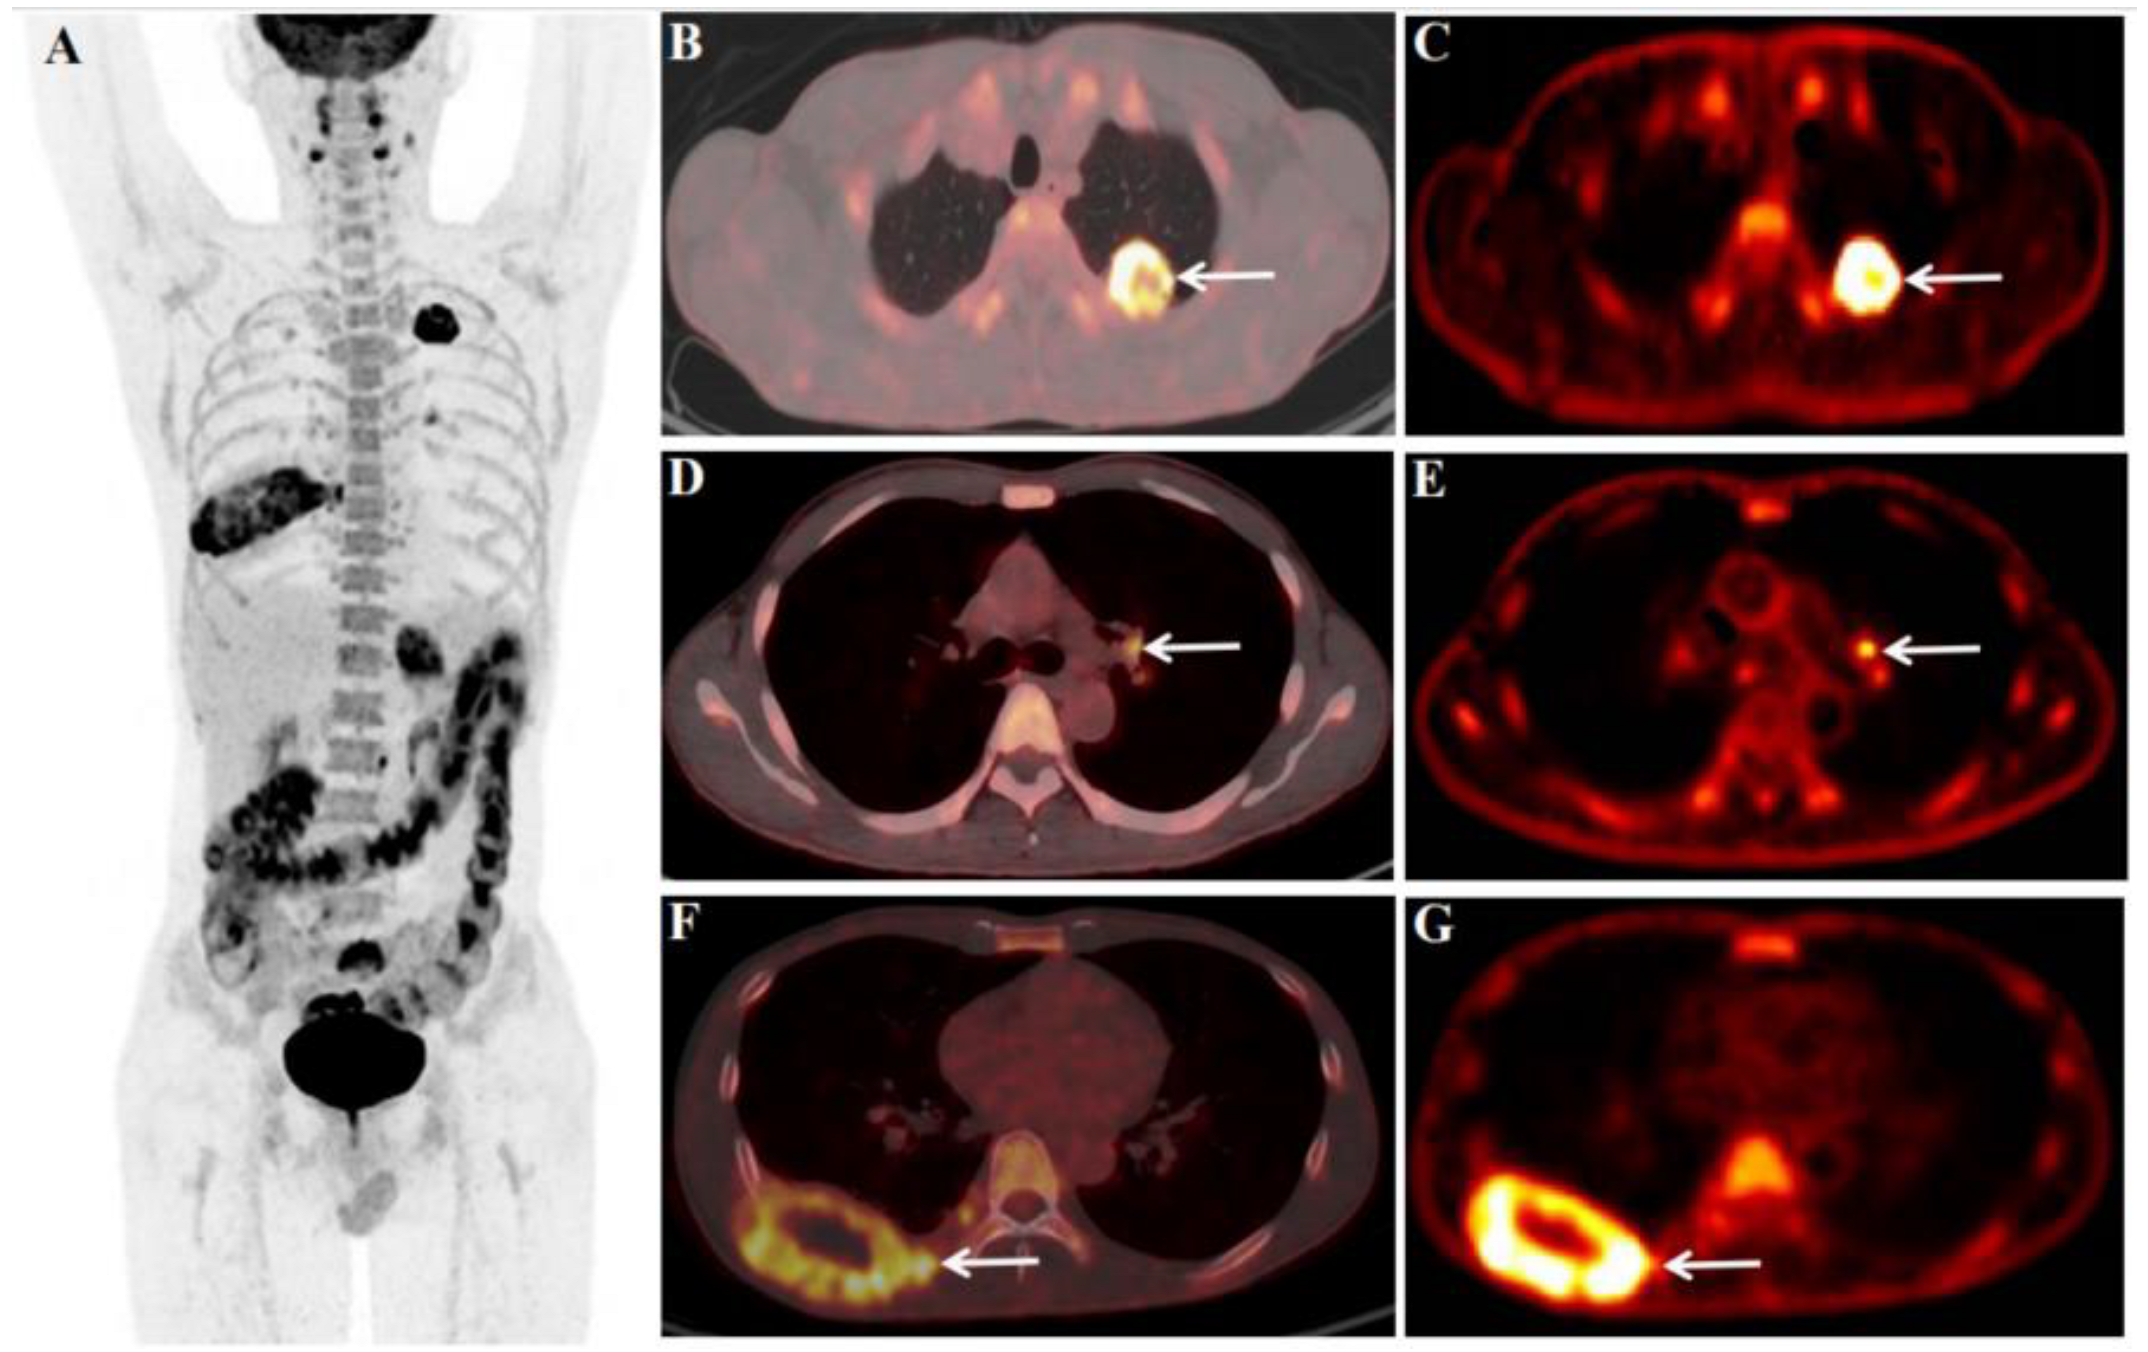

![[⁶⁸Ga]Ga-tilmanocept PET/CT lymphoscintigraphic images of the same ...](https://www.researchgate.net/publication/357378954/figure/download/fig4/AS:1146753294315529@1650418699730/GaGa-tilmanocept-PET-CT-lymphoscintigraphic-images-of-the-same-patient-as-illustrated.png)